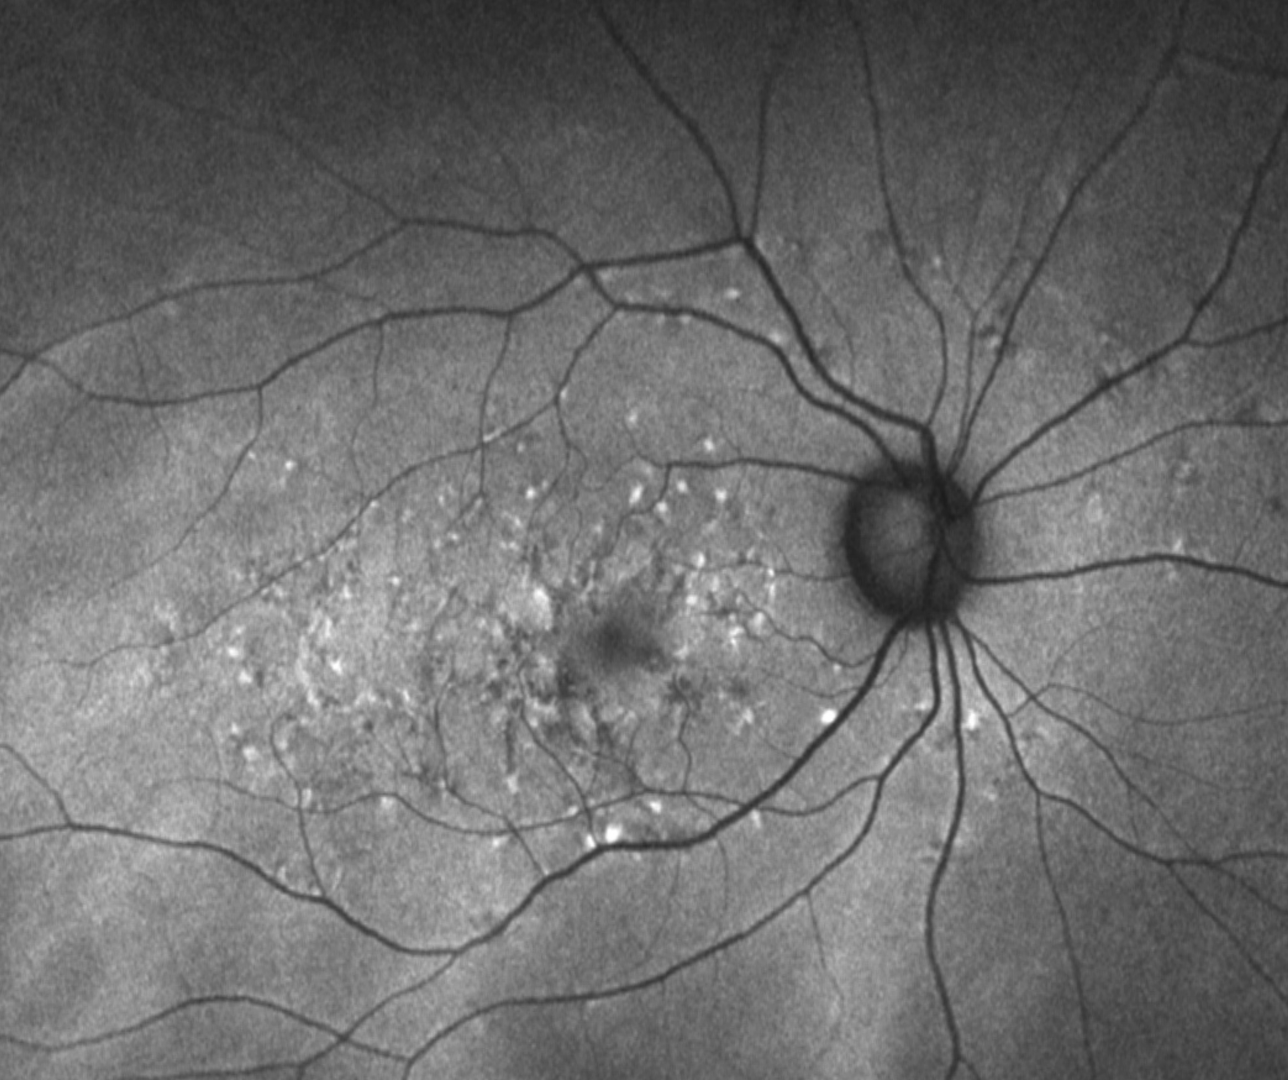

• Inherited Retinal Degenerations (IRD)

Inherited Retinal Degenerations (IRD)

Inherited retinal degenerations (IRDs) encompass a large group of clinically and genetically heterogeneous diseases that can lead to progressive vision loss.